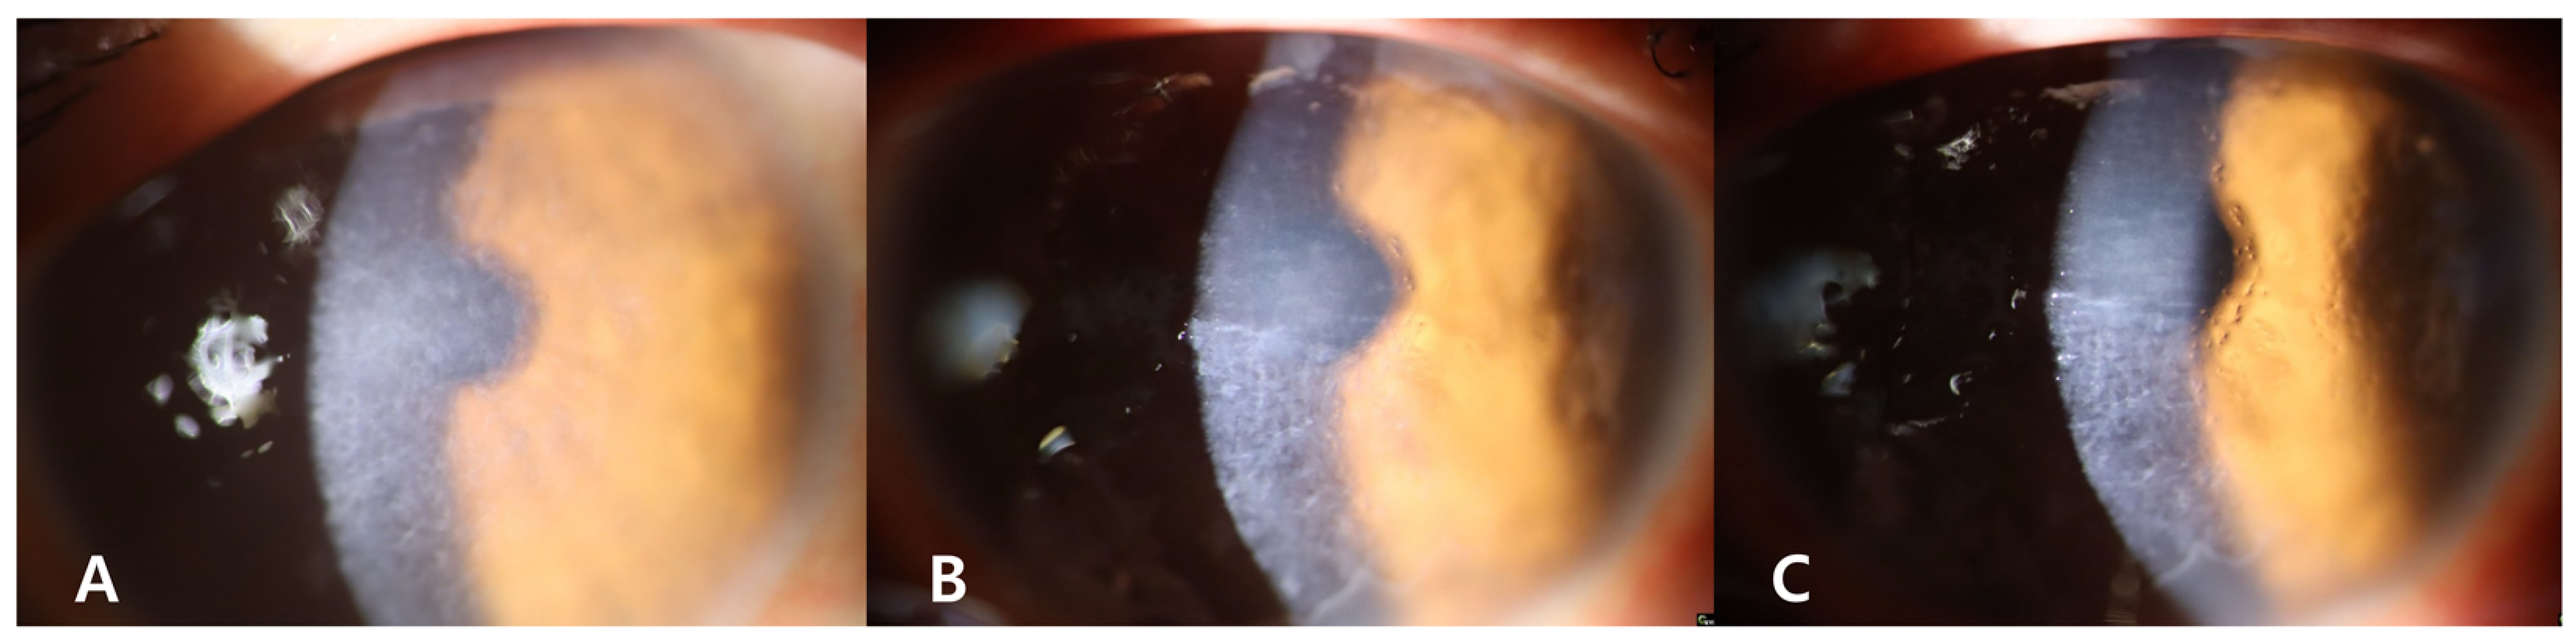

2. Case Presentation

2.3. Phototherapeutic Keratectomy (PTK)